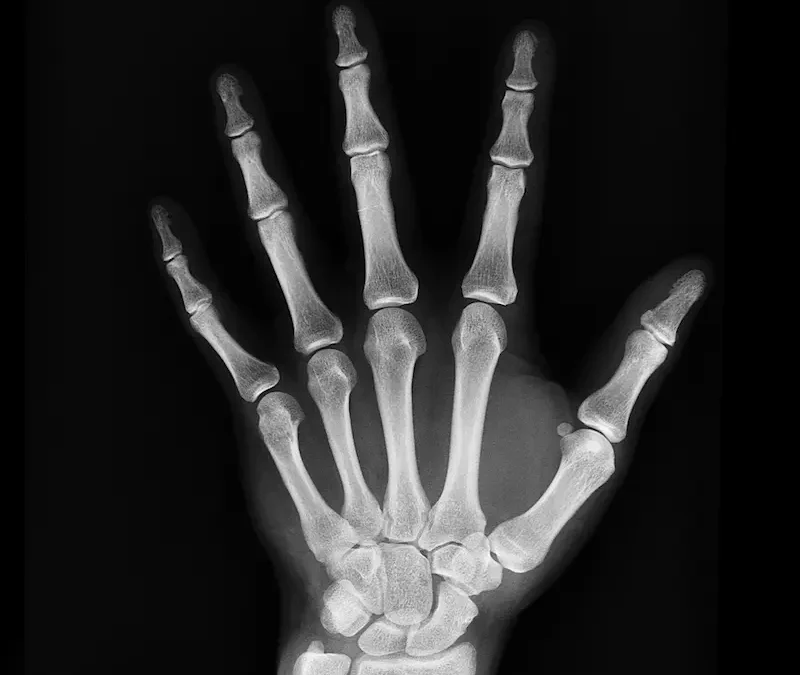

Señala el Dr. Guedez que el hueso es ante todo «una estructura vida» y que nuestro sistema óseo está compuesto por 106 huesos, cuya función está más allá de sostener nuestro cuerpo.

Imagen de Monoar Rahman Rony en Pixabay

Precisamente en la médula ósea se producen los glóbulos rojos, blancos, además de plaquetas; pero además el huesos tienen funciones hormonales y de reserva de minerales. Por ello, afirma Guedez, «hay que darles mantenimiento», para alejarnos de la osteoporosis.